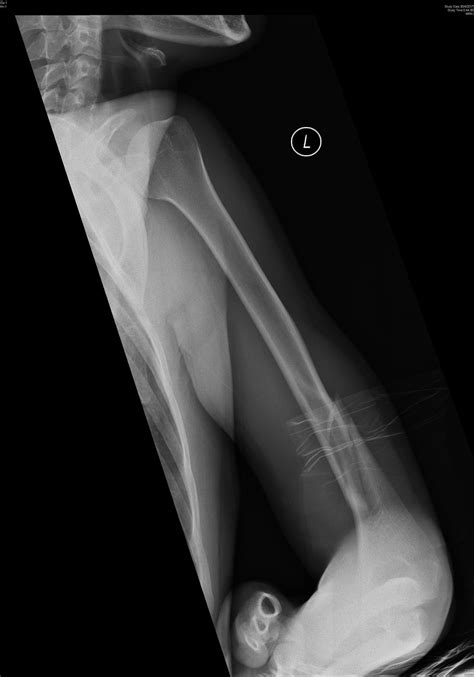

X-ray showing a humerus fracture

Upon reaching a medical facility, doctors will typically order imaging tests to confirm the diagnosis. An X-ray is the standard diagnostic tool to visualize the location and severity of the fracture. In more complex or intra-articular cases, a CT scan may be requested to better map the bone fragments for surgical planning.

However, if the bone is unstable, severely displaced, or involves the joint surface, surgery is often the preferred route. A procedure known as Open Reduction Internal Fixation (ORIF) is commonly performed. During this surgery, an orthopedic surgeon repositions the bone fragments and secures them with hardware, such as metal plates, screws, or intramedullary nails.